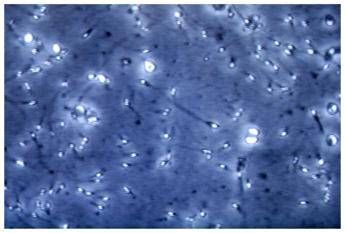

Analizzando campioni di liquido seminale provenienti da uomini sani con parametri nella norma, i ricercatori hanno individuato microplastiche in tutti i sei campioni esaminati. Le particelle osservate hanno dimensioni molto piccole, comprese tra circa 2 e 13 micrometri. Si tratta di dimensioni estremamente ridotte: pochi micrometri corrispondono infatti a grandezze paragonabili a quelle degli spermatozoi stessi, la cui testa ha un diametro di circa 5-8 micrometri.

“Uno degli aspetti più rilevanti emersi dallo studio è che le microplastiche, pur essendo presenti nel liquido seminale, non aderiscono agli spermatozoi e non penetrano al loro interno”, si legge nello studio. Le particelle risultano disperse nel plasma seminale e coesistono con le cellule senza stabilire un’interazione diretta. “Questo dato è importante perché indica che, almeno per le microplastiche di queste dimensioni, non osserviamo un contatto diretto con gli spermatozoi – sottolinea il professor Andrea Di Nisio dell’Università Pegaso, co-autore dello studio – Ciò non significa che il problema sia irrilevante, ma che eventuali effetti potrebbero essere mediati da meccanismi indiretti, legati piuttosto alle strutture riproduttive che le microplastiche attraversano prima di arrivare al liquido seminale, come ad esempio testicoli, epididimo e prostata”.